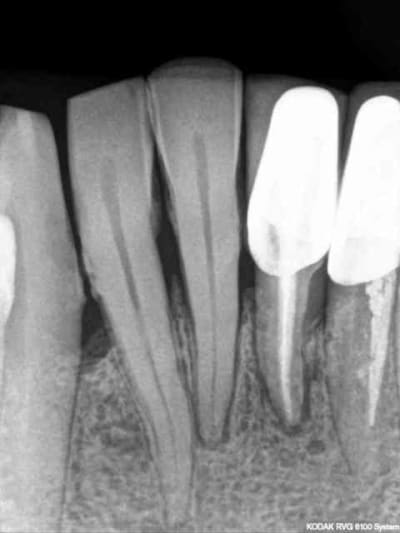

1)2)3) suite à de vilaines bactéries mangeuses d'apex (pas alapex, hein! lui il est immangeable) 31 est extraite 15 jours avant implantation.

4)j'aurai bien volontiers retiré 32 également mais le patient ne veut pas (pour l'instant).